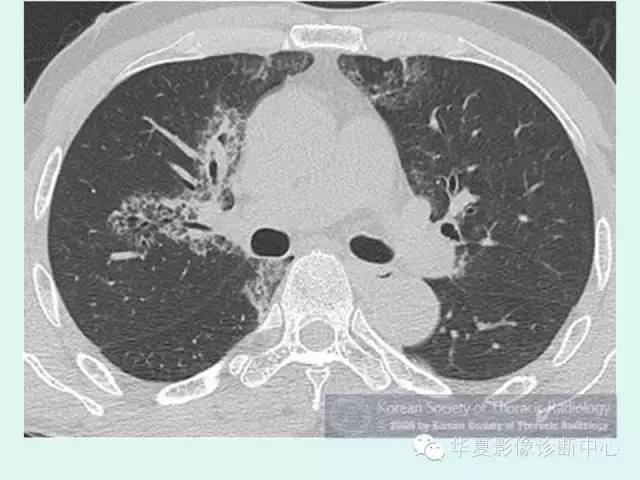

【病例】肺泡蛋白沉积症1例CT影像表现